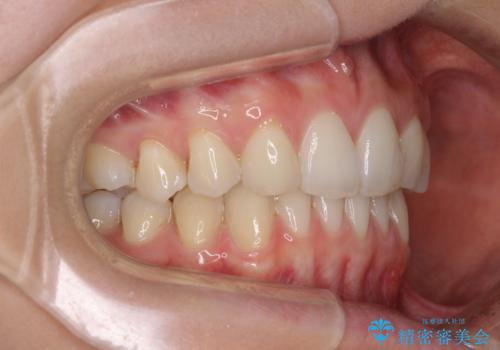

上顎前歯が2本欠損 インビザラインによる叢生の解消

- 深い咬み合わせと前歯のデコボコを気にして来院された患者様です。

上顎前歯2本が欠損しているため、妥協的なゴールを設定しインビザラインで矯正治療を行うこととしました。

上下前歯の大きさのアンバランスにより、深い咬み合わせと奥歯の咬みにくさがなかなか解決されず、治療に長期間を要することとなりました。